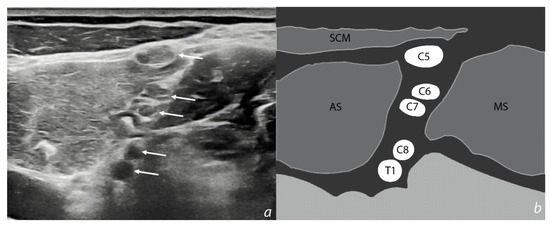

6.3. Imaging

- Bianchi, S.; Martinoli, C. Ultrasound of the Musculoskeletal System; Springer: Heidelberg, Germany, 2007. [Google Scholar]